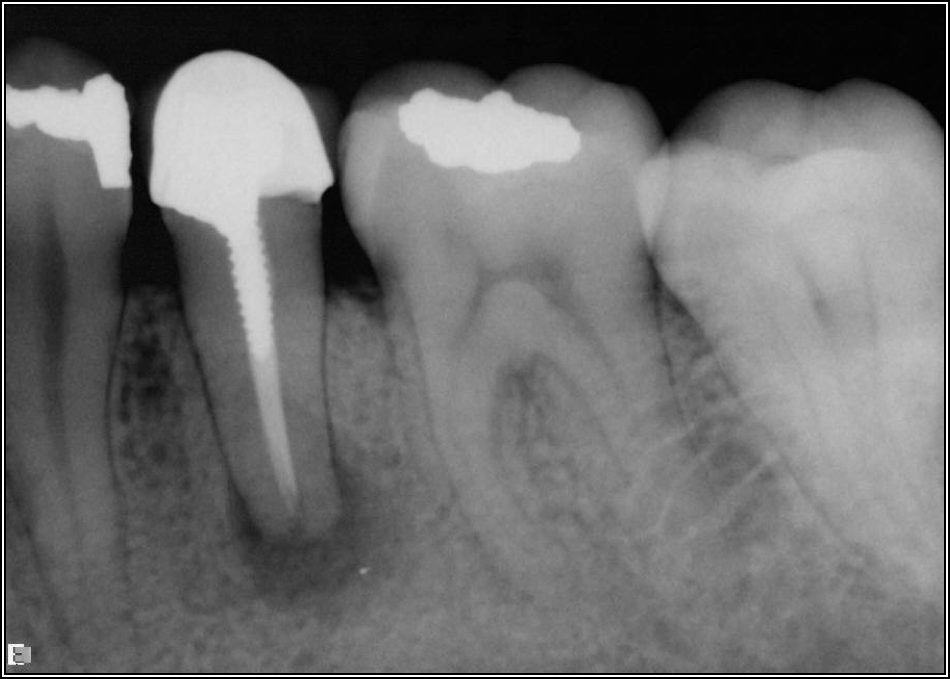

If a tooth stands alone, greater forces will be placed on it because it has no adjacent teeth to provide support. This situation will affect the decision-making process for placing a post. Figure 3 shows a tooth that was on an island and would be having three implants placed in front of it. The tooth would take a much greater beating than another tooth that had support proximally. Even though it had a good root canal, the clinician would need to account for whether the tooth would last until the implants integrated. Figure 4 shows a case that would quickly proceed to implants. The patient had a less-than-ideal bridge for over a decade, with decent endodontics and functionality. There was also an overhang on the premolar. The post was not ideal in this case because there was one distal canal and not all the gutta-percha was removed from it. An intimate fit should be the goal with the post and the walls. Whether using a threaded or non-threaded post, there should not be excess gutta-percha because it is not as solid as the tooth and will lead to greater movement. That movement on the tooth and bridge will create too much force and result in demise.

Fig 3. Tooth on an island.

Figure 3

Fig 4. Case that quickly would proceed to implants.

Figure 4